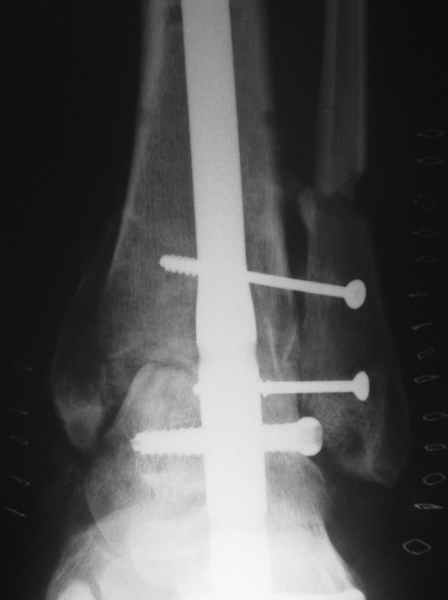

Nail arthrodesis for failed pilon fracture is good solution.

My example

В этом плане артродез на гвозде очень выигрывает - нет гипса, очень стабильная фиксация, нагрузку на ногу можно давать практически с первого дня и боли в значительной степени меньше т.к. операция малотравматична и фиксация стабильная. Конечно, методика не идеальна, не свободна от осложнений и имеет свои проблемы и нюансы.